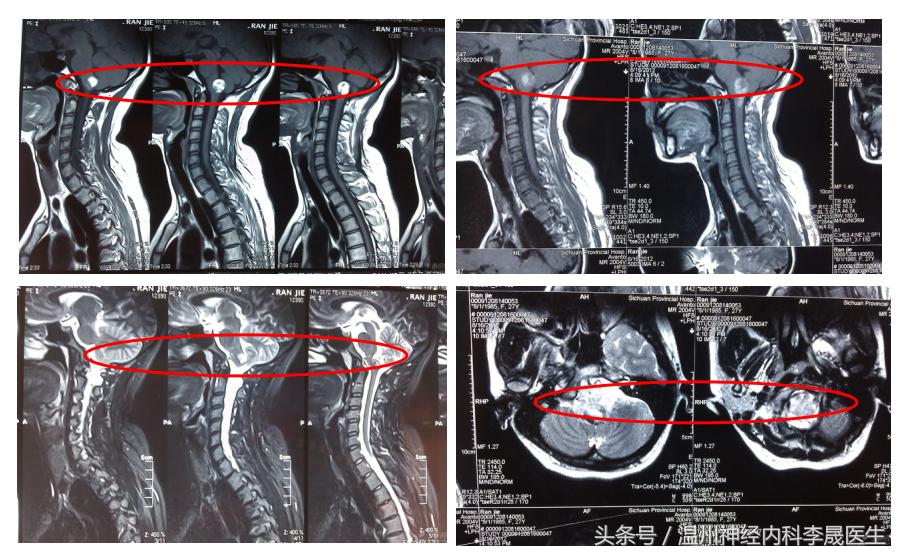

延髓出血(MRI)